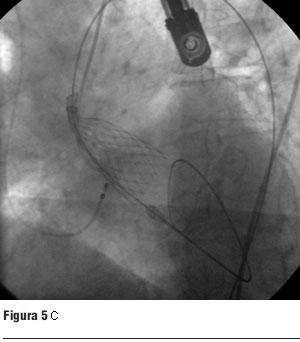

Luego de la valvuloplastia y en el menor tiempo posible se procedió al avance y posicionamiento de la válvula percutánea, con posterior liberación de la misma (figura 5 a, b, c y d).

Figura 5. Prótesis CoreValve expandida en posición aórtica.